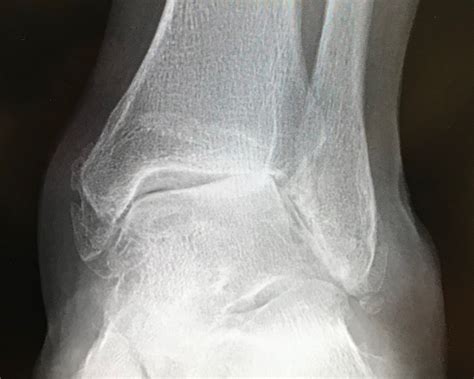

• Severe Arthritis: When arthritis has progressed to the point where it causes significant pain and limits mobility, ankle fusion surgery may be necessary.

• Fractures: Complex fractures that do not heal properly or result in instability may require ankle fusion surgery to restore stability and function.